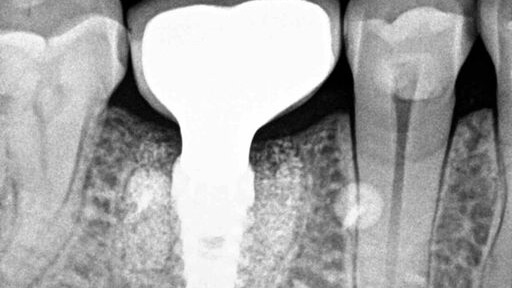

Bone Augmentation Prior To Implant Placement: A Review And Case Report

There is no doubt that the advent of dental implants has revolutionized the field of dental medicine. With the ability to esthetically and functionally replace single teeth or act as abutments for dentures, implants show not only versatility in application, but also innovation in the way in which we treat our patients. Implants also demonstrate … Read more